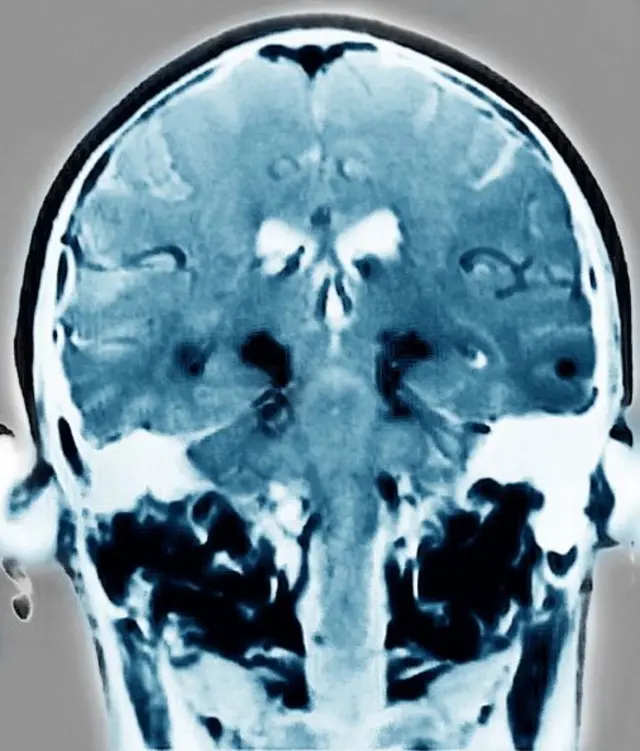

పార్కిన్సన్స్ తీవ్రం కావడం అంటే మెదడు అనారోగ్యం త్వరగా పెరుగుతూ ఉంటుంది.

పార్కిన్సన్స్ సోకిన వాళ్లకు మెదడులో డోపమైన్ అనే రసాయనం తగినంత ఉండదు. ఎందుకంటే దాన్ని ఉత్పత్తి చేసే నాడీ కణాలు దెబ్బ తినడం వల్ల ఇలా జరుగుతుంది.

మెదడులో కణాలు దెబ్బ తిని నాడీ సంబంధిత లక్షణాలు కనిపించకముందే వ్యాధిని త్వరగా గుర్తించడం వల్ల త్వరగా చికిత్స ప్రారంభించవచ్చు.